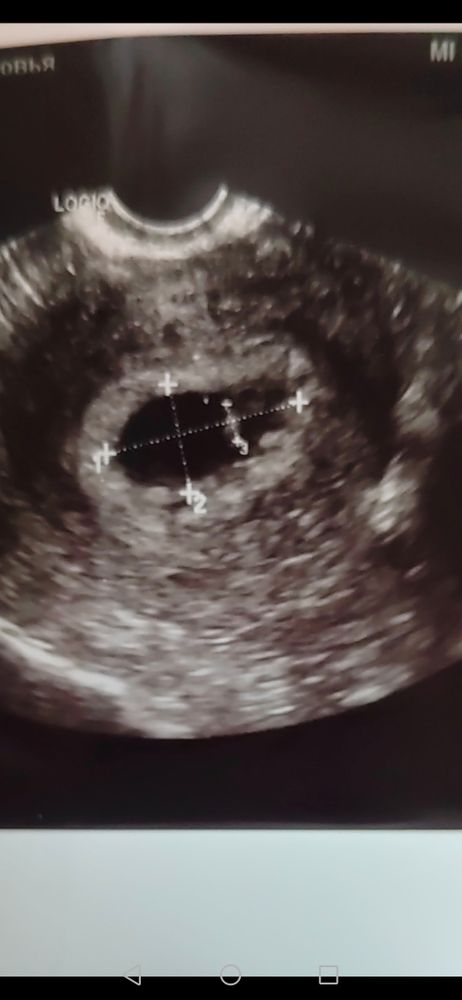

Интересно попробовать, тем более, что скоро узнаю пол точно) сделала всё, как вы сказали, только вот не могу понять, на моем фото хориона больше по правой стороне?

Это 8+4

Ваше предложение? Интересно послушать